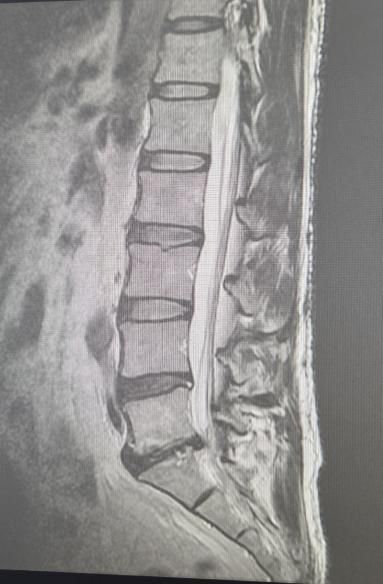

제mri사진 올리겠습니다

• 1번 째 사진

사진을 통해서 보았을 때 L4-L5 디스크도 살짝 탈출증이 있으며, L5-S1 사이의 디스크는 심하게 있어 보입니다. 영상만 두고 보았을 때에는 디스크의 정도가 경미해 보이지는 않지만, 실제로 영상으로 보이는 것과 증상의 정도가 명확하게 상관관계를 가지는 것은 아닙니다. 디스크가 심하게 밀려있고 척추를 누를 수 있긴 하지만, 그럼에도 증상은 심하지 않을 가능성이 존재합니다.